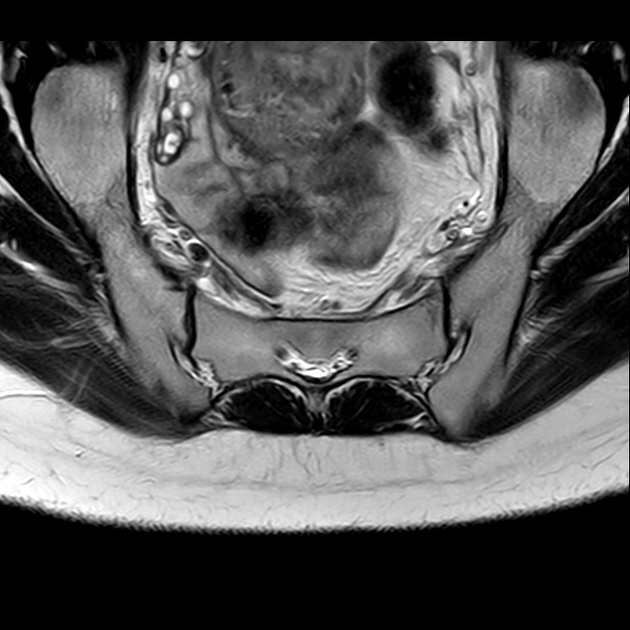

磁共振检查:

T1

6、磁共振上可以发现骨折线周边明显的骨髓水肿,增强扫描明显强化

磁共振影像表现